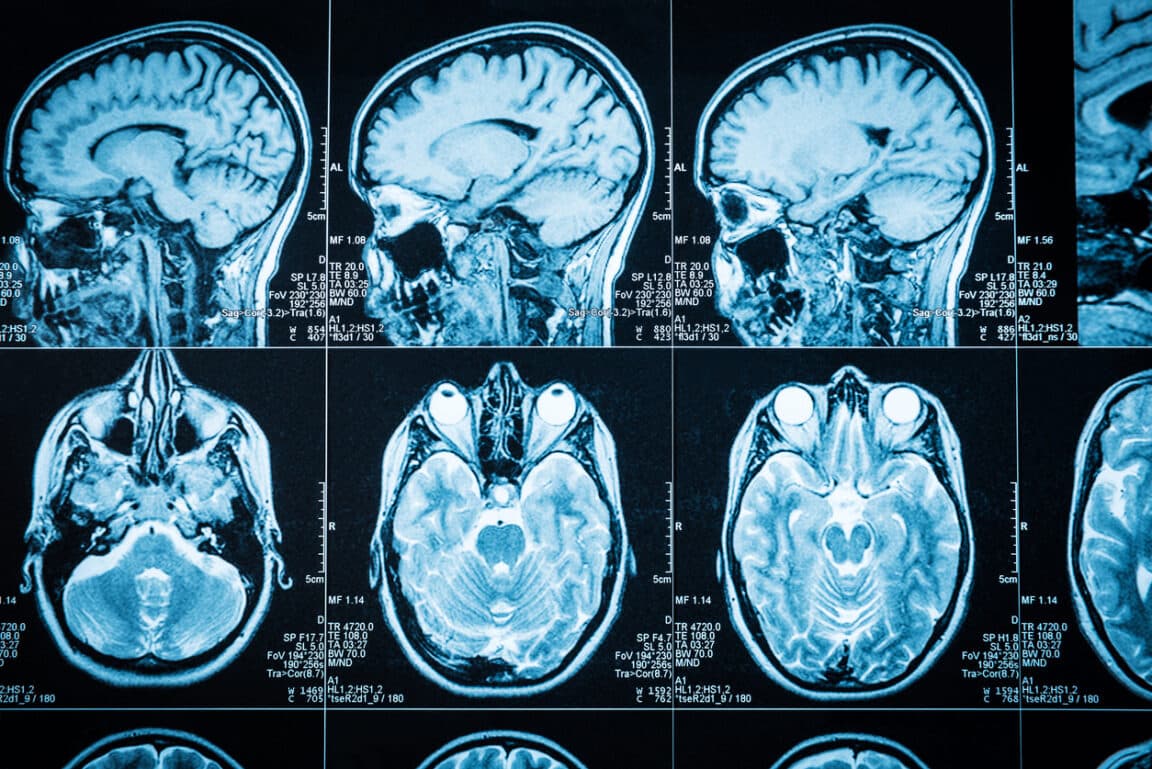

Une étude parue dans la revue Frontiers in Psychiatry le 14 février 2023 souligne un autre effet de la cocaïne sur le long terme. Les chercheurs de l’Université Heidelberg à Mannheim (Allemagne) évoquent en effet un vieillissement biologique prématuré du cerveau.

Afin d’arriver à cette conclusion, les scientifiques ont tenté de comprendre comment une drogue était capable d’exercer une influence sur les jonctions entre les cellules cérébrales et être à l’origine des conséquences néfastes que tout le monde connaît. Par ailleurs, l’étude s’est basée sur l’analyse de 42 tissus cérébraux humains post-mortem, dont 21 appartenaient à des consommateurs de cocaïne.

Les auteurs de l’étude ont focalisé leur attention sur la zone Broadman 9 (BA9) qui se trouve dans le cortex préfrontal. Or, celle-ci est en lien étroit avec la conscience de soi ainsi que le contrôle inhibiteur, deux notions fortement perturbées par la prise de cocaïne. Concrètement, il s’agissait d’observer les niveaux de méthylation de l’ADN dans cette région, à savoir des modifications chimiques s’accumulant avec l’âge. Selon les résultats, les consommateurs réguliers de cocaïne avaient davantage de sections d’ADN intégrant des groupes méthyles. Autrement dit, ces personnes ont biologiquement vieilli plus rapidement que leur âge réel, en comparaison avec des individus n’ayant pas consommé la drogue.